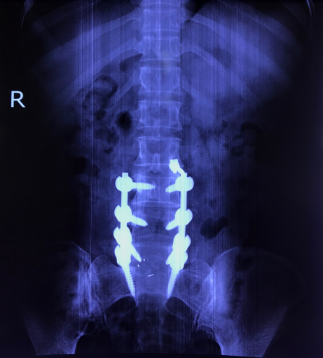

Hình ảnh: X Quang bệnh nhân sau phẫu thuật hàn xương, nắn chỉnh cột sống

Cho tới nay, phương pháp phẫu thuật nắn chỉnh trượt, cố định cột sống bằng nẹp vít qua cuống, ghép xương liên thân đốt lối sau (sử dung Cage) được cho là hiệu quả nhất, áp dụng phổ biến nhất để điều trị trượt đốt sống thắt lưng.